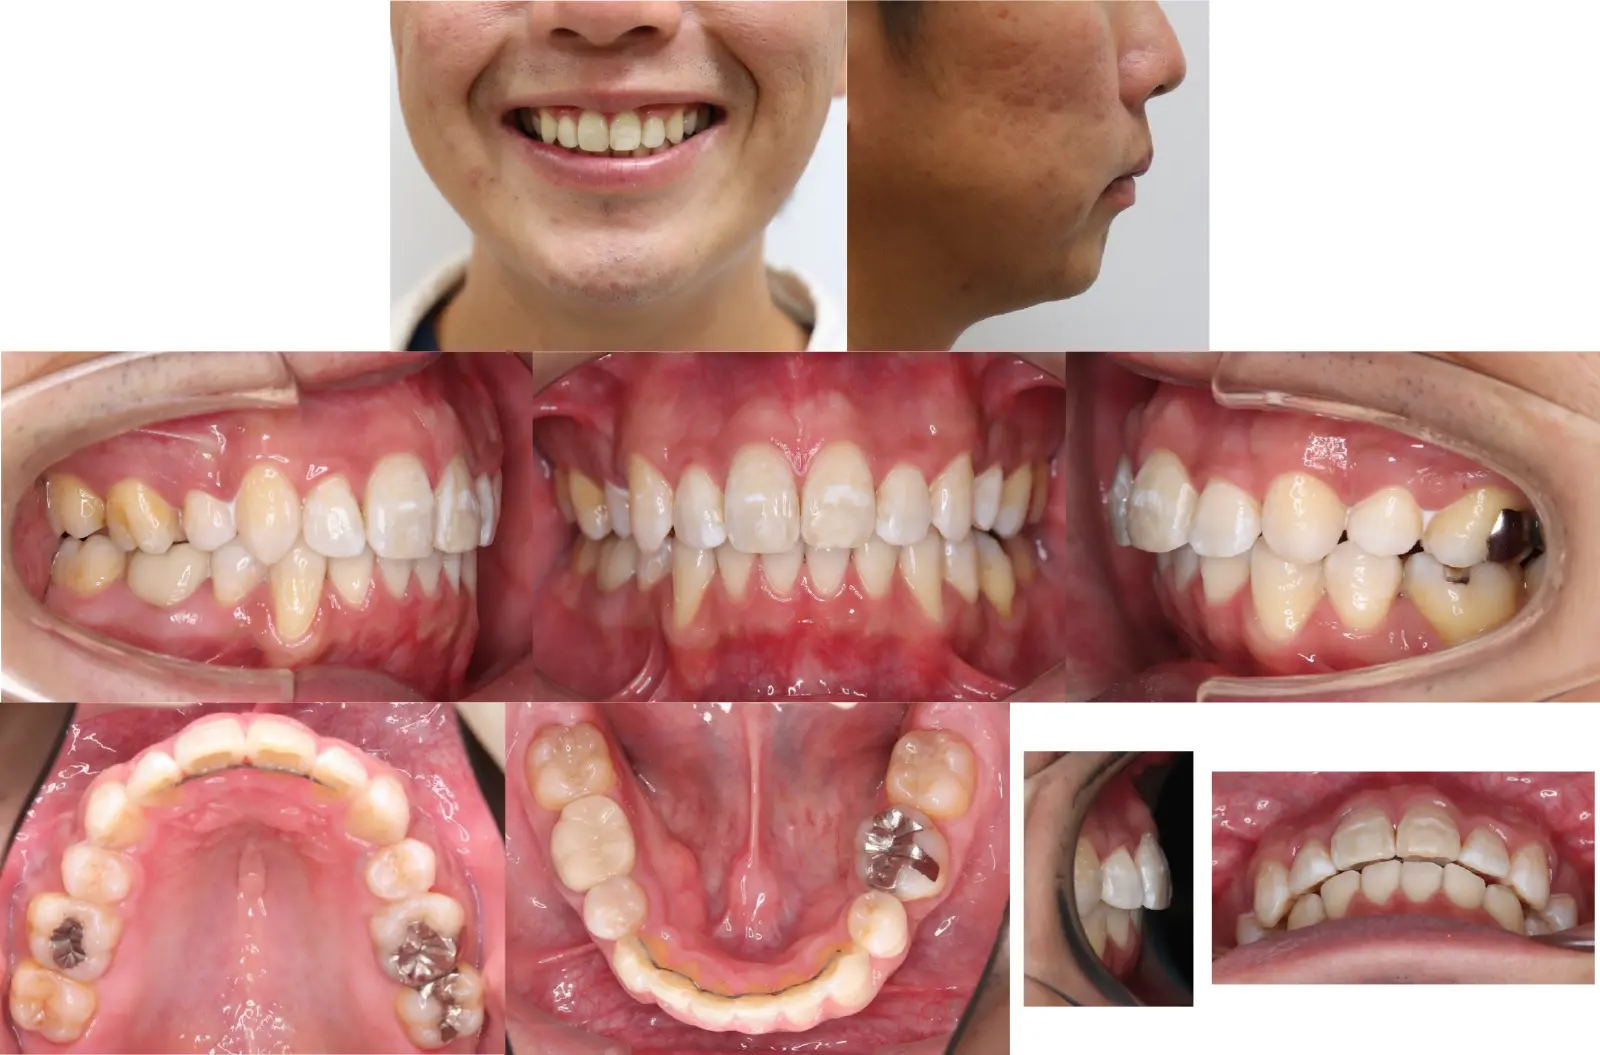

Angle Ⅱ級、叢生を伴う上顎前突症

- 主訴

出っ歯と乱食い歯

- 年齢

30代

- 治療期間

3年4ヶ月

- 治療回数

32回(コロナのため来院できず)

- 治療に用いた主な装置

カスタムメイド型リンガルブラケット矯正装置 (WIN)

i-station(アンカースクリューによる矯正装置)

- 治療費

1,400,000円(税別)トータル料金

- 抜歯部位

上顎と下顎右側は第一小臼歯、下顎左側第二小臼歯を抜歯。